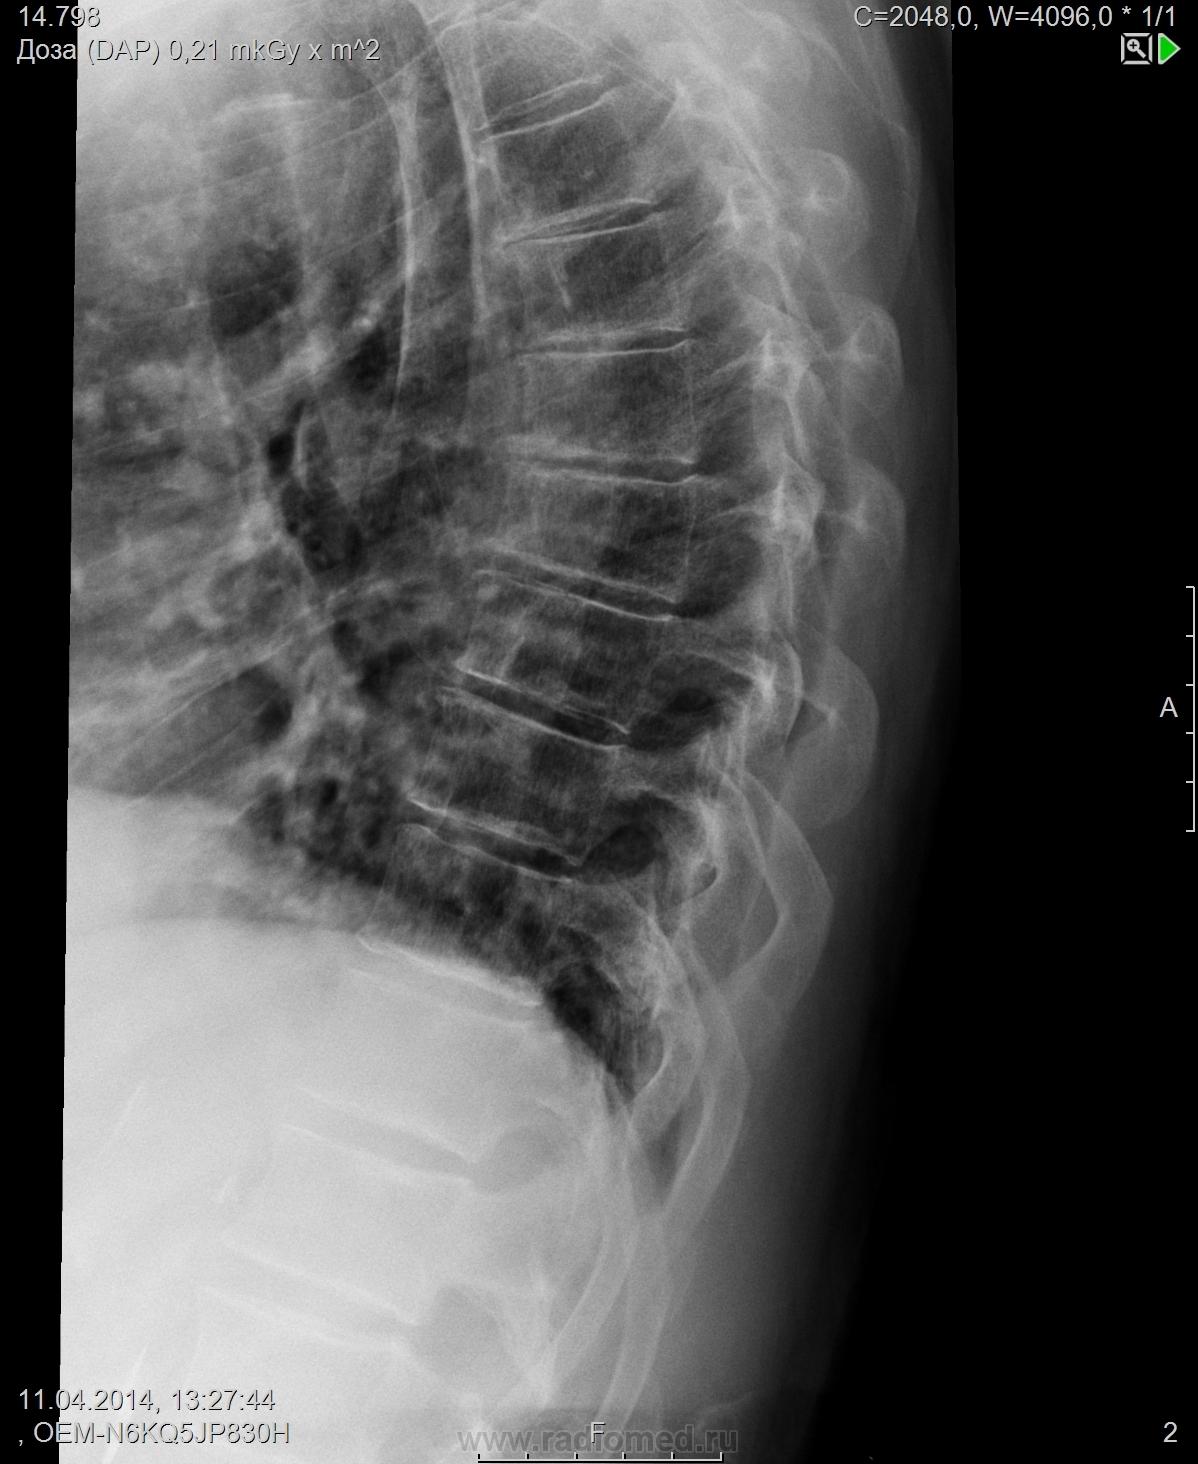

Правосторонний сколиоз до 10 градусов. Снижена высота передних краев позвонков ThVI, ThVII, с признаками клиновидной деформации. Локальное усиление кифоза на уровне ThVI - ThVII. Боковые остеофиты ThX-XI, ThXI-ThXII.

Заключение: Рг картина дегенеративного спондилеза, правостороннего сколиоза 1 ст, компрессионный перелом ThVI, ThVII?

Это клиновидность как признак дегенеративных изменений. За переломы сомнительно.

Остеохондроз грудного отдела, III период, остеопороз тел позвонков. Костно-травматических изменений не выявлено.